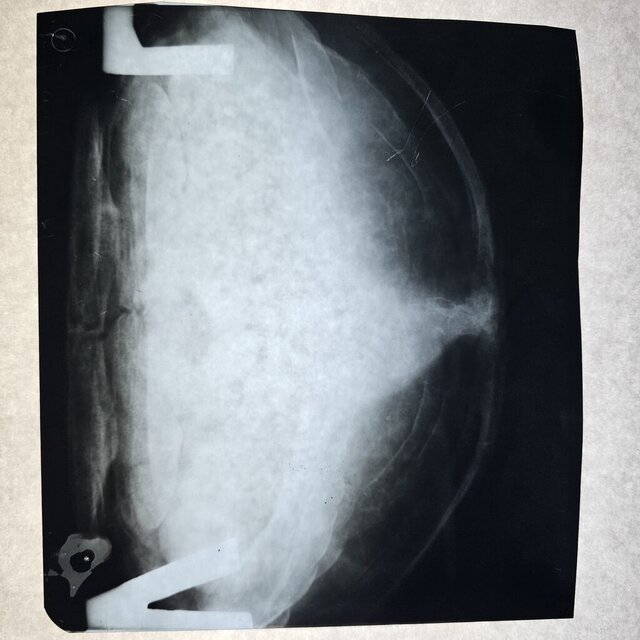

Добрый день. Сходили в клинику Степаненко в Харькове, но приём вела не она. Сдали кровь её удалось взять очень мало. Сделали ренген. Получили назначения. Там нам вкололи Элеовит. Сказали что все очень плохо. Анализ крови скину завтра клиника не прислала

Назначения из клиники